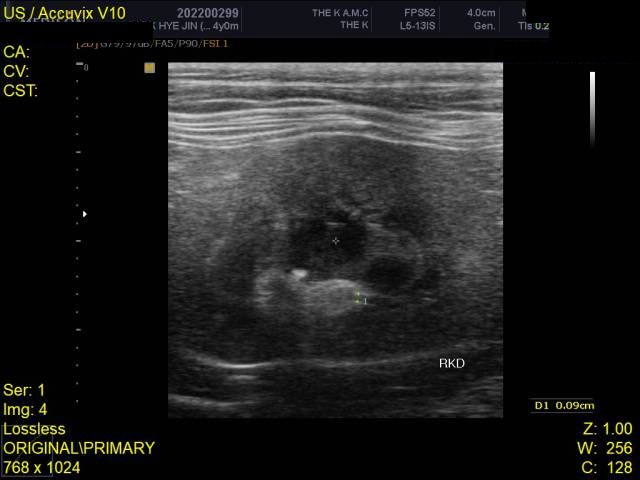

HCM의 진단의 golden standard 는 심장초음파 검사입니다. 하지만 첨부된 자료에는 심장 초음파 검사 결과가 없고

흉부 방사선 검사 또한 외측상이 결여되어 있어 자료로 판단할 수 없습니다.

주치의에게 요청하여 심장 초음파 검사를 진행해 보시기 바랍니다.